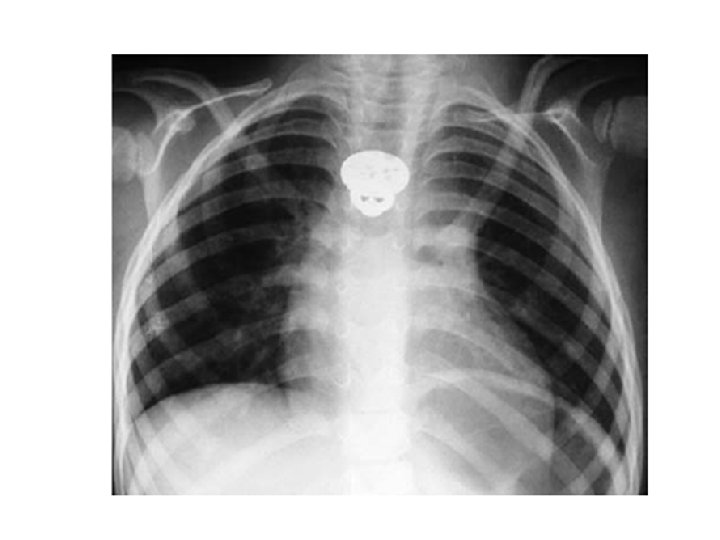

Foreign Body in the Oesophagus • Common sites are the cervical constriction, broncho-aortic constriction and diaphragmatic constriction. • Common foreign object: coin, dentures, bone • Treatment: antibiotics, endoscopic removal, thoracotomy